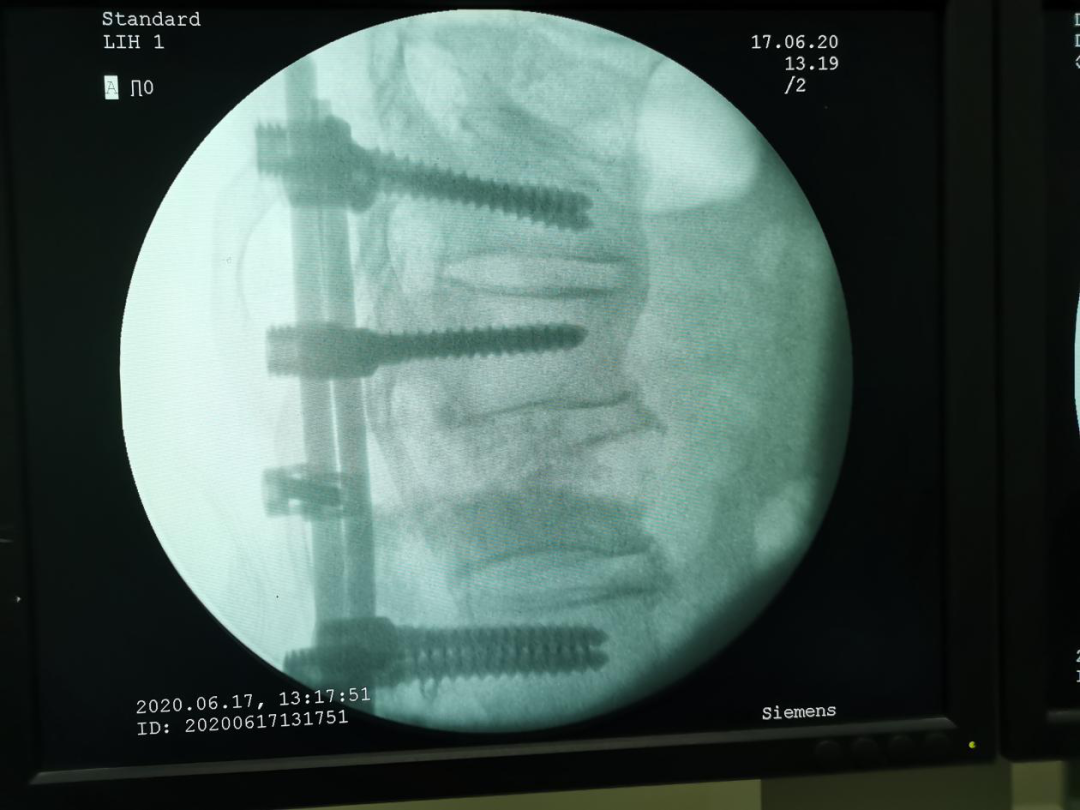

第二个科室是脊柱外二科,也是脊柱中心主任的科室。这里有脊柱大夫所钟爱的各种手术,有脊柱开放手术,也有经皮内固定、脊柱微创手术,可谓一个技术全面的科室。一台脊柱手术需要的时间一般较长,因科室手术很多,每个大夫的工作量都很大,他们的技术都很好,能够保证一台一台的手术按时完成。